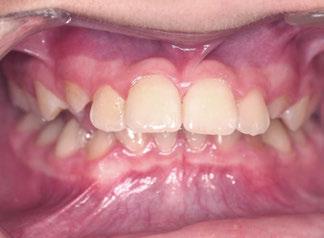

Exploración Intraoral

Presenta un estado oral deficitario. Parcialmente edéntula, con colapso de mordida, migración dental patológica, restauraciones de resina antiguas fisuradas y filtradas, transparencia y exposición de cámara pulpar secundaria a desgastes con pérdida de estructura e integridad de tejido dental importante (Figuras 1 a 4). Portadora a tiempo parcial de prótesis removibles desadaptadas de más de 10 años de antigüedad, refiriendo incapacidad de adaptación a este tipo de prótesis.

Exploración extraoral

Se constata reducción del tercio facial inferior produciendo a nivel estético una apariencia envejecida por formación de surcos en las comisuras labiales («líneas de marioneta») secundarias a una disminución de la dimensión vertical por desgaste dental (Figuras 5 y 6).